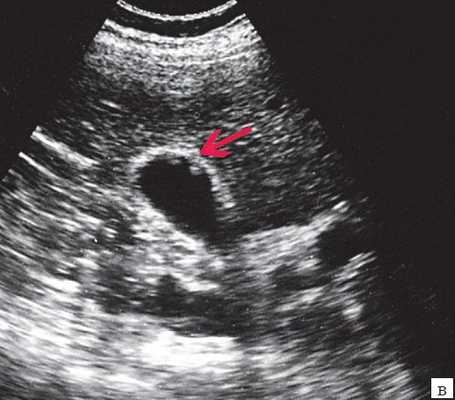

Ультрасонография является эффективным средством выявления полиповидной формы холестероза 6. Традиционной считается следующая сонографическая характеристика холестериновых полипов: неподвижные гиперэхогенные структуры, которые не дают акустической тени и прикрепляются к стенке желчного пузыря. Контуры таких образований, как правило, ровные, а размеры таких образований различны, чаще не превышают 10 мм (рис. 2).

в) Полиповидно-сетчатая форма холестероза, полипы размерами до 5 мм, повышенной эхогенности.

Мелкие холестериновые включения, образующие диффузную сеточку в толще подслизистого слоя размерами 1-2 мм, выглядят как локальное утолщение или уплотнение стенки желчного пузыря и в некоторых случаях (см. рис. 2) вызывают реверберацию (эхографический симптом "хвост кометы").